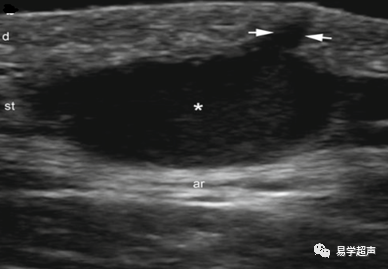

Ximena Wortsman.Dermatologic Ultrasound with Clinical and Histologic Correlations.Springer New York Heidelberg Dordrecht London,2013.